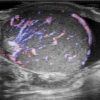

Viêm tinh hoàn - mào tinh

Viêm tinh hoàn – mào tinh

» Thông tin: Nam giới – 34 tuổi.

» Lâm sàng: Sưng đau vùng bìu.

# Tăng kích thước và tín hiệu mạch trên doppler tinh hoàn và mào tinh hoàn.